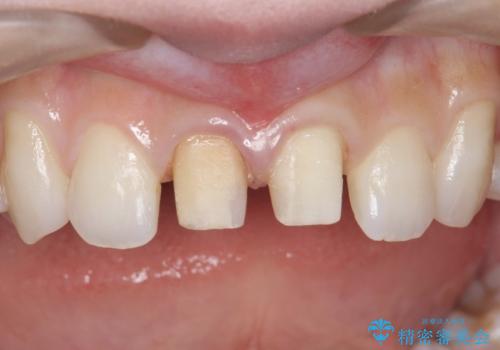

前歯の変色 セラミックで ホワイトニングも併用

- 神経のない前歯が変色していたため、矯正治療後にセラミックで修復しました。

セラミックの前に、全体をオフィスホワイトニング(エクセレント)して周りの歯を白くして色をなじませました。

右の前歯は当院で根管治療をやり直しています。(根管治療はDr.大元が担当しました。)